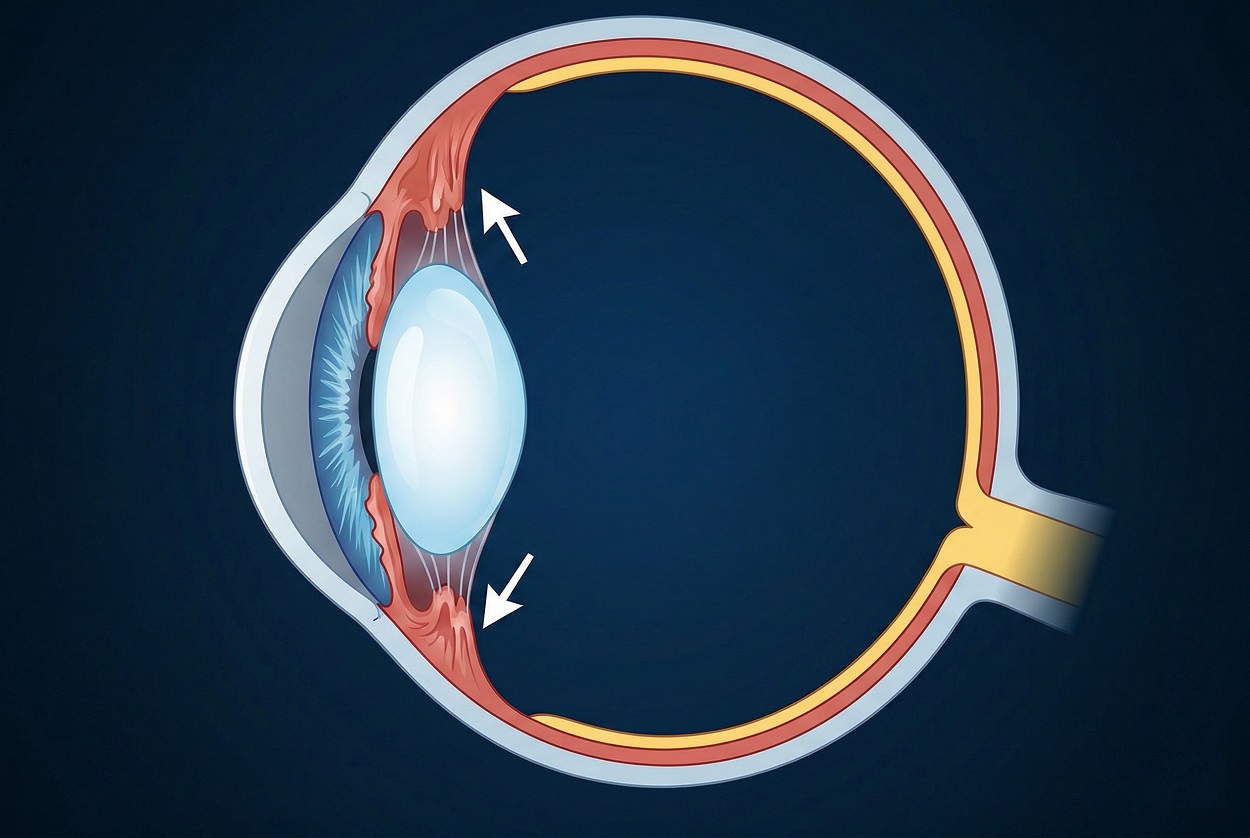

3. Миф о том, что чтение в темноте портит зрение

Чтение при слабом освещении часто считают причиной ухудшения зрения.

Недостаток света действительно увеличивает нагрузку на зрительную систему. Зрачки расширяются, а цилиарная мышца работает активнее для фокусировки. Это может вызывать зрительное утомление, сухость глаз и головную боль.

Однако эти эффекты носят временный характер и проходят после отдыха. Современные исследования не подтверждают прямую связь между чтением при слабом освещении и развитием близорукости у взрослых.

При этом у детей важную роль играет общий уровень освещения в течение дня. Дефицит яркого естественного света действительно ассоциирован с повышенным риском миопии.